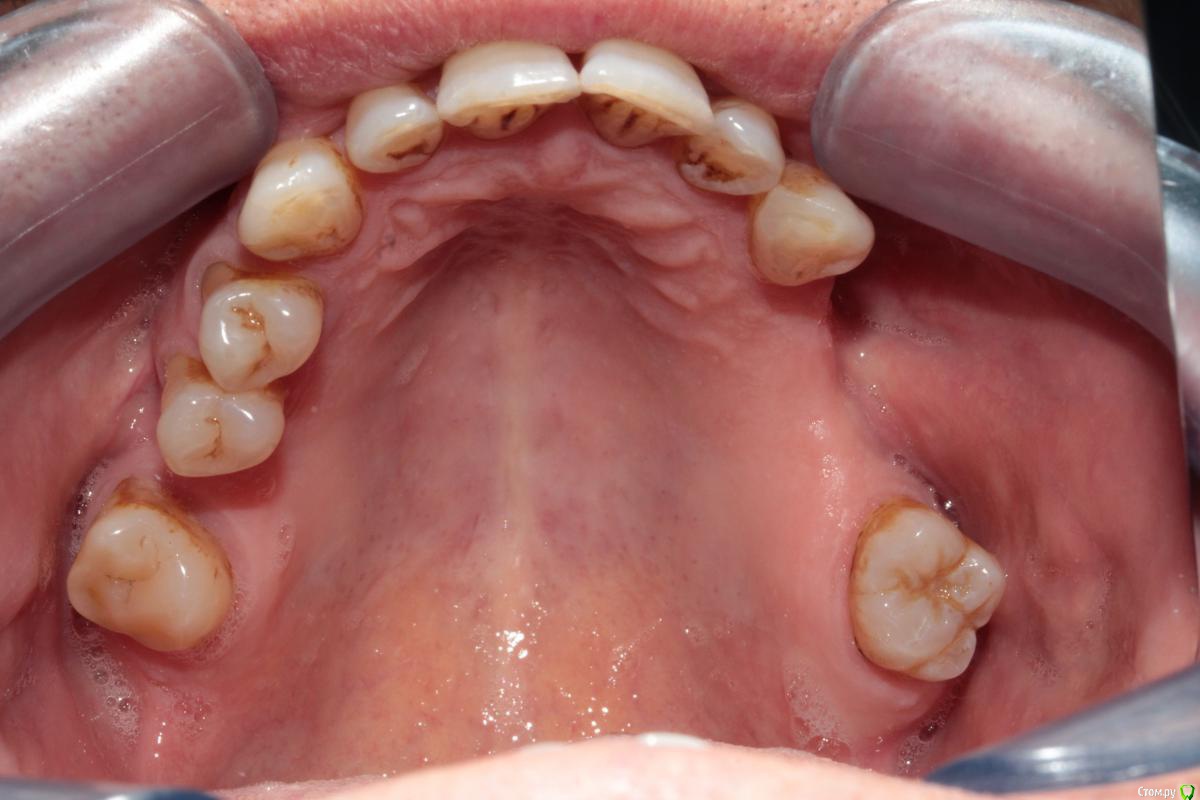

Здравствуйте уважаемые коллеги. Прошу у Вас совета какой план лечения вы бы рекомендовали данному пациенту.

Сразу замечу, я сначала рассматривал вариант с ортодонтией (чтобы собрать все зубы вместе) а далее в отсутствующие места имплантация. Но, пациент не в силах оплатить это лечение. Так как пациент мой бывший учитель, я хочу ему помочь, сделать работу которая материально минимально затратна и функционально его обеспечит.

37ой зуб я уже удалил, сначала сделал ревизию, обнаружен был кариес корня по фуркации, поэтому удалили. На данный момент пациент не может полноценно жевать.

Меня больше смущает 2 момента, 1й - это то что на верхней челюсти зубы "разбросаны" как попало, не знаю что можно сделать не собрав их вместе предварительно. 2ой - в 4ом сегменте мост, консольный, его снимать не хочется, так как его по сути недавно поставили, а не сняв его не знаю что можно сделать в 3ем сегменте, если имплантацию откидываем как вариант....

Был предложен вариант сделать бюгель, с обычными кламмерами на верхней челюсти, как думаете при таком расположении зубов, это правильно?